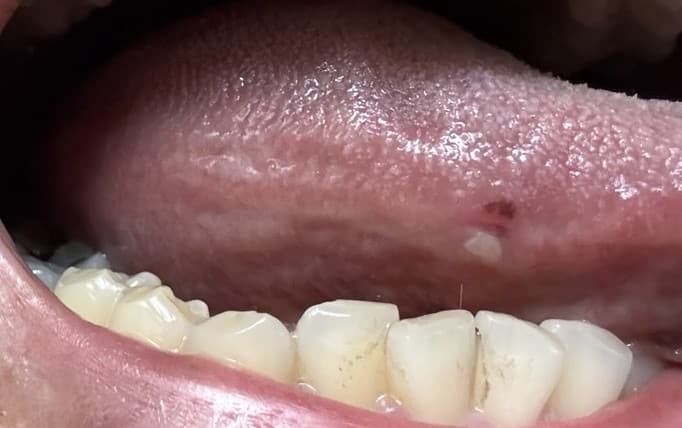

혀옆 하얀병소 설암같은건 아닐까 걱정되요

1주일전에 첫번째사진처럼 상처가났었구요

(자다가 갑자기 통증이생겨서 깼어요)

아침에 확인해보니 피물집이생겼었다가

저녁엔 사진처럼 하얀물집으로 바꼈는데요

지금 시간이지나서 보니 두번째이후사진을 처럼

변했는데..

낫고있는건가요?

아니면 병원을 한번 가봐야되나요

아프거나 그러진않아요

혀가 씹히면서 상처가 난 것으로 암과는 거리가 있어보이니 너무 걱정하지 않으셔도 됩니다.

혀가 자극을 받앗거나 씹혀서 생긴거 같습니다. 큰 문제가 잇는건 아니니 너무 걱정하지마세요.